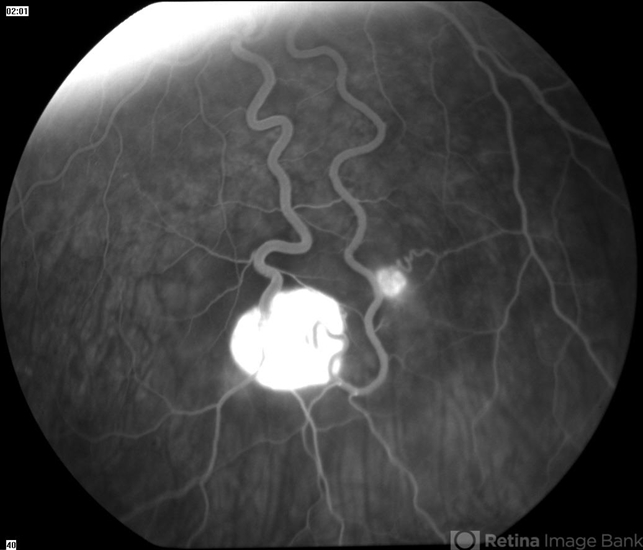

- VHL angioma

- Von Hippel-Lindau, hemangioma

- Mid phase fluorescein angiogram of 16 year old male with recent diagnosis of Von Hippel-Lindau disease showing hyperfluorescent angiomas in inferior mid periphery OD.